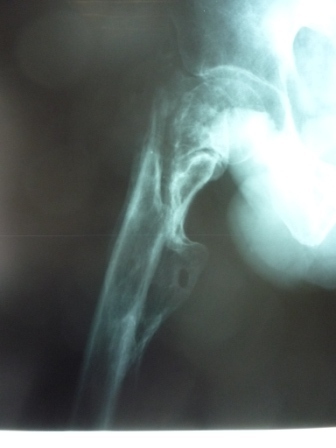

[Ortho] Сросшийся со смещением чрез-подвертельный перелом

Больной Н. 44 года травма 1,5 года назад июнь 2008 года чрез-под вертельный  перелом правого бедра. Во время лечения у больного развился алк делирий,  проводилось консертативное лечение перелома.

Беспокоят боли, укорочение конечности.

Укорочение 3 см. Ногу поднимает,  сгибание ограничено, ротационные движения в полном объеме.

Что делать?

Протез? Если <да> Можно ли обойтись стандартной ножкой Corail?

Или межвертельная остеотомия?